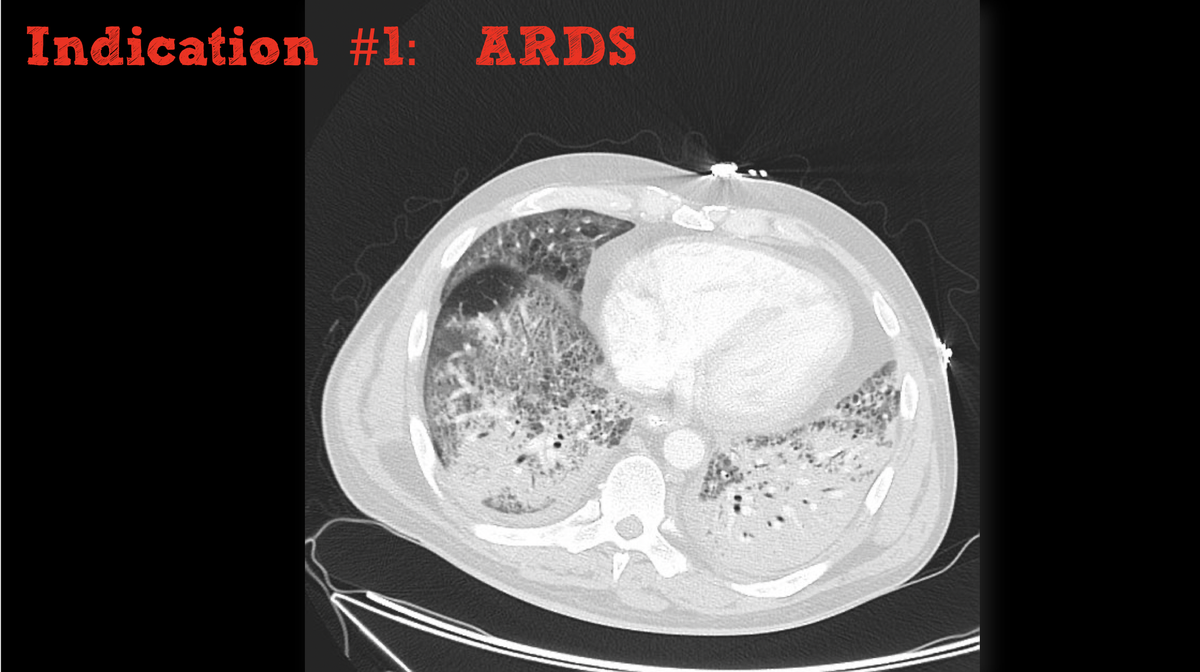

When managing the sickest patients with RV failure or hypoxemia, these can come in clutch.

- Can improve oxygenation

- May bridge patients failing conventional therapy (e.g. buying time to prone or recruit with APRV)

- Doesn't modify underlying dz process